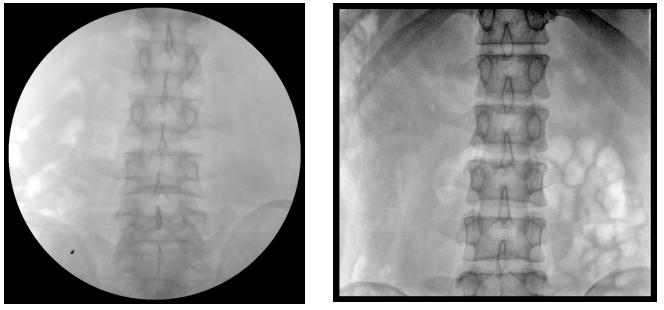

【產(chǎn)品臨床圖片】